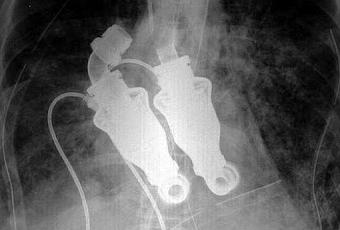

El checo Jakub Halik es el primer hombre del mundo que sobrevive desde hace ya seis meses sin corazón, después de que el suyo fuera extirpado para ser sustituido por dos bombas.

El paciente, un bombero de 37 años, tenía un tumor maligno en el corazón, y la única alternativa que se le ofrecía en lugar de un trasplante inmediato era la implantación de las bombas, una que manda la sangre por la aorta, y la otra a los pulmones. Un órgano completo sustituido por un dispositivo, ¿esto es posible? Veamos que si, lo es!.

Lo más costoso fue fijar la presión de bombeo de cada uno de los dispositivos, pues la sangre que va a los pulmones debe tener menor presión para que éstos no se irriten. El único inconveniente es cargar con las pilas bajo los brazos. Los acumuladores no se ven, no pesan mucho y duran entre 8 y 12 horas, mientras que el equipo regulador se lleva como una riñonera. En el caso de Halik, las revoluciones están fijadas para una actividad normal, no para correr, hacer deporte ni subir por una escalera. “No es capaz de reaccionar al esfuerzo”, aseveró Pirk.

Hay que aclarar que Halik ha sido el segundo en la historia que ha recibido un corazón artificial sin pulso, es decir, no tiene válvulas. "La experiencia confirma que la vida útil de las bombas es de 5 o 10 años. Pero desde un punto de vista biológico, es difícil responder a la pregunta", dijo la doctora checa Netuka a través del sitio web Medical Tribune. Solo el tiempo dirá que tan bueno es este tan útil soporte de vida, hasta ahora a demostrado se eficaz, dando el tiempo necesario hasta que a Halik le puedan transplantar un corazón biológico.